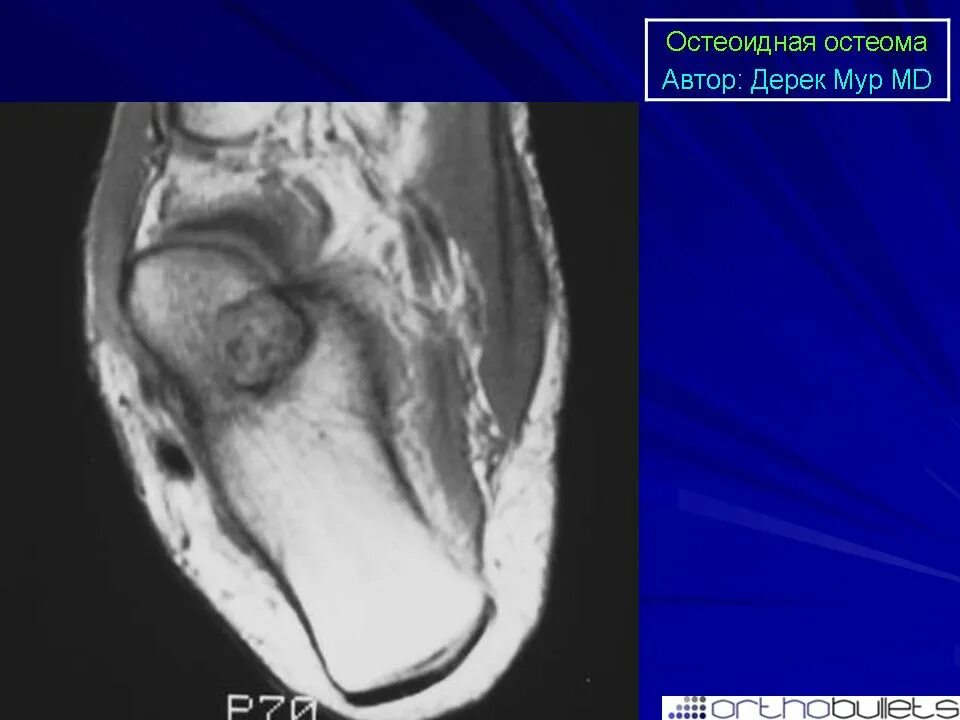

Остеома мрт